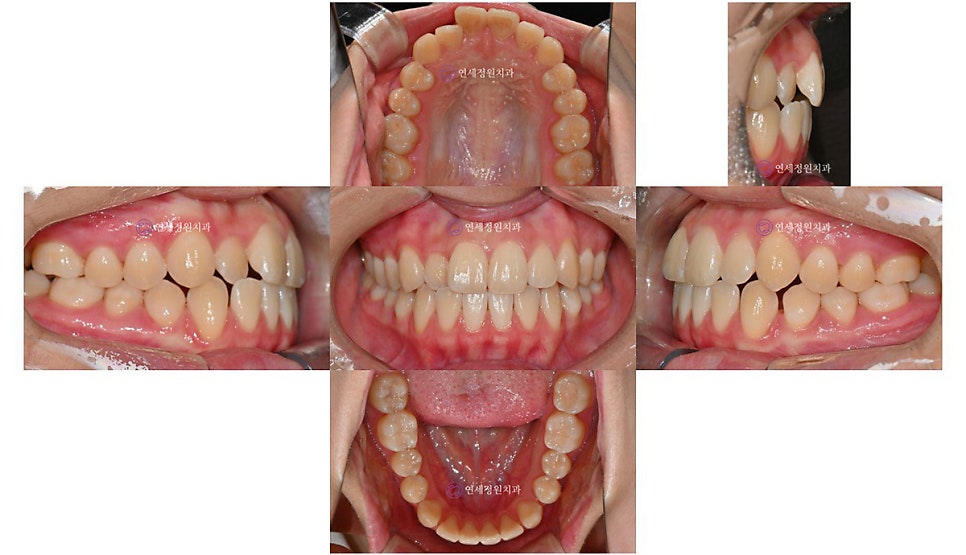

그리고 얼마 전 오랫만에 저희 연세정원치과로 환자분께서 찾아왔을 때는 이미 키가 거의 170cm가 다 된 숙녀가 되어있었습니다 :) (원래 악세서리는 다 제거하고 찍어야 하지만... 엑스레이 상에서도 여기저기 피어싱이 보이네요 ㅎㅎ) 방학이라 한국에 잠시 들른 동안 정기 검진을 받으러 왔는데, 위 앞니 하나가 틀어져 있고 입이 살짝 돌출이라 2차 교정 상담을 하셨으나, 한달 뒤 출국 일정 때문에 부분교정을 하기에도 시간은 부족한 상태였습니다.

2024년 7월

군입대를 하는 분들이나 외국 유학을 가는 환자들의 경우 종종 인비절라인을 추천드리고 있습니다. 인비절라인 투명교정의 경우 구강스캔한 자료를 바탕으로 클린체크라고 하는 치료 계획에 맞추어 단계별로 전체 장치가 제작되어 나오기 때문에 유학생의 경우에도 교정을 할 수 있다는 장점이 있습니다. 물론 정기적으로 내원하여 체크 받는 것이 가장 좋긴 하지만, 처음에 치료 계획을 잘 세우고 환자분도 장치를 열심히 잘 착용해준다면 내원하지 않고도 충분히 교정이 가능합니다.

이 환자분께서는 인비절라인으로 틀어진 앞니와 약간의 돌출감을 개선하기로 하였고, 한달 뒤 장치가 나오면 내원하여 어태치먼트도 붙이고 장치를 착용할 준비를 한 후 장치를 받아 출국하기로 하였습니다. 대략 1~1년 반 뒤에 귀국 예정이라 중간중간 사진을 찍어 보내주시면 중간 진행 상황을 확인을 해드리기로 했습니다. 인비절라인의 경우 교정이 잘 마무리되게 되면 외국에 계속 거주하시더라도 인비절라인의 비베라 유지장치를 캐나다로 배송해드릴 수 있다는 장점도 있습니다.